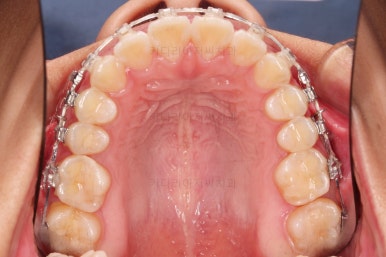

1. 초진 시 입안의 모습 평가

부산연산역치아교정 키다리아저씨치과에 처음 내원했을 당시의 입안의 모습이비다.

앞니 약간, 어금니쪽 약간 삐뚤어진 것, 그리고 위아래 앞니가 약간 뻗쳐 보이는 양상 이외에는 매우 가지런해 보여서 교정치료를 굳이 왜 하시려고 하지? 라고 생각될 정도의 치열 상태였습니다.